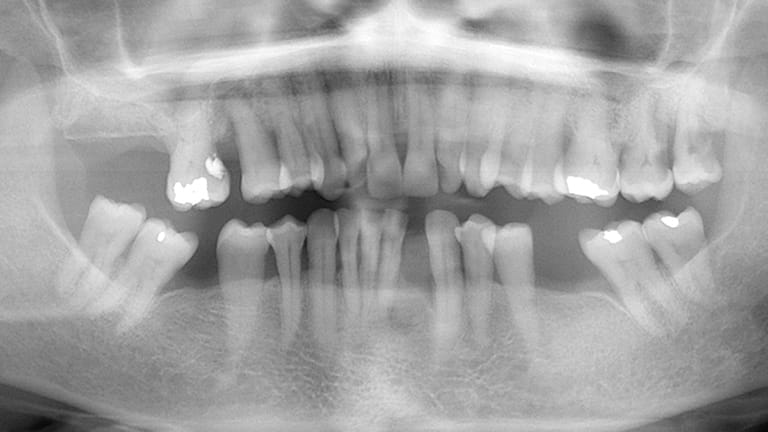

Single Tooth Replacement

Bad Tooth

Below is a few examples of what DENTAL IMPLANTS can do for you and your smile!